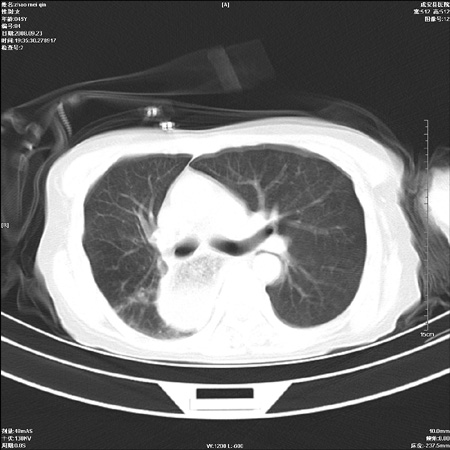

标题: CT15861:女 60 外伤后1小时 胸疼 [打印本页]

标题: CT15861:女 60 外伤后1小时 胸疼

外伤后1小时 胸疼 是外伤后引起的吗?

食道扩张明显下端逐渐变窄,倒像贲门失迟缓

非外伤性改变,典型的贲门失迟缓症

食道扩张明显下端逐渐变窄,大量食物存留,象贲门失迟缓症。